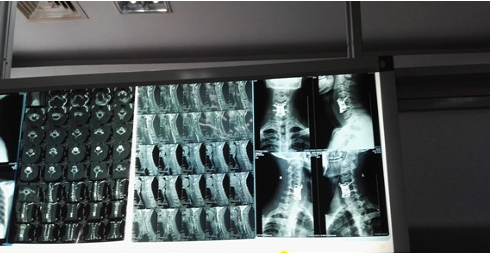

今年42歲的李先生,幾個月前突然左側(cè)肩背痛并反復(fù)出現(xiàn)午后高熱的情況,在被家人送入當(dāng)?shù)蒯t(yī)院后,由于醫(yī)療條件有限,一直未查明病原。9月15日,李先生轉(zhuǎn)入江西省人民醫(yī)院,專家在對李先生進行會診后,根據(jù)磁共振及患者一系列表現(xiàn),診斷為頸椎結(jié)核。

“磁共振顯示第五、第六位置的頸椎完全被炎癥侵蝕,同時,我們還發(fā)現(xiàn)該患者病變進展較快,椎管內(nèi)膿腫已擠壓脊髓。”據(jù)主治醫(yī)師董謝平主任介紹,他們考慮到病變的頸椎椎體均只剩1/3尚未發(fā)生骨質(zhì)破壞,但卻已被結(jié)核的炎癥所浸潤,原本全為松質(zhì)骨的椎體無法對螺釘提供足夠的握持力。因此,必須將第五、第六位置的椎體全長切除,并將其兩端的椎間盤一并切除,用自體骨塊或鈦網(wǎng)可自體骨等填充缺損、支撐在第四椎體下緣和第七椎體上緣之間,另用鋼板固定第四到第七椎體前緣,并在椎體上各擰入兩枚約1.5cm長的鎖定螺釘。“這種長節(jié)段固定的初衷讓螺釘固定于較堅實的正常椎體上,但跨距過大的鋼板,其固定強度顯然不如短節(jié)段固定,固定節(jié)段越長,劣勢越明顯。”董主任說。